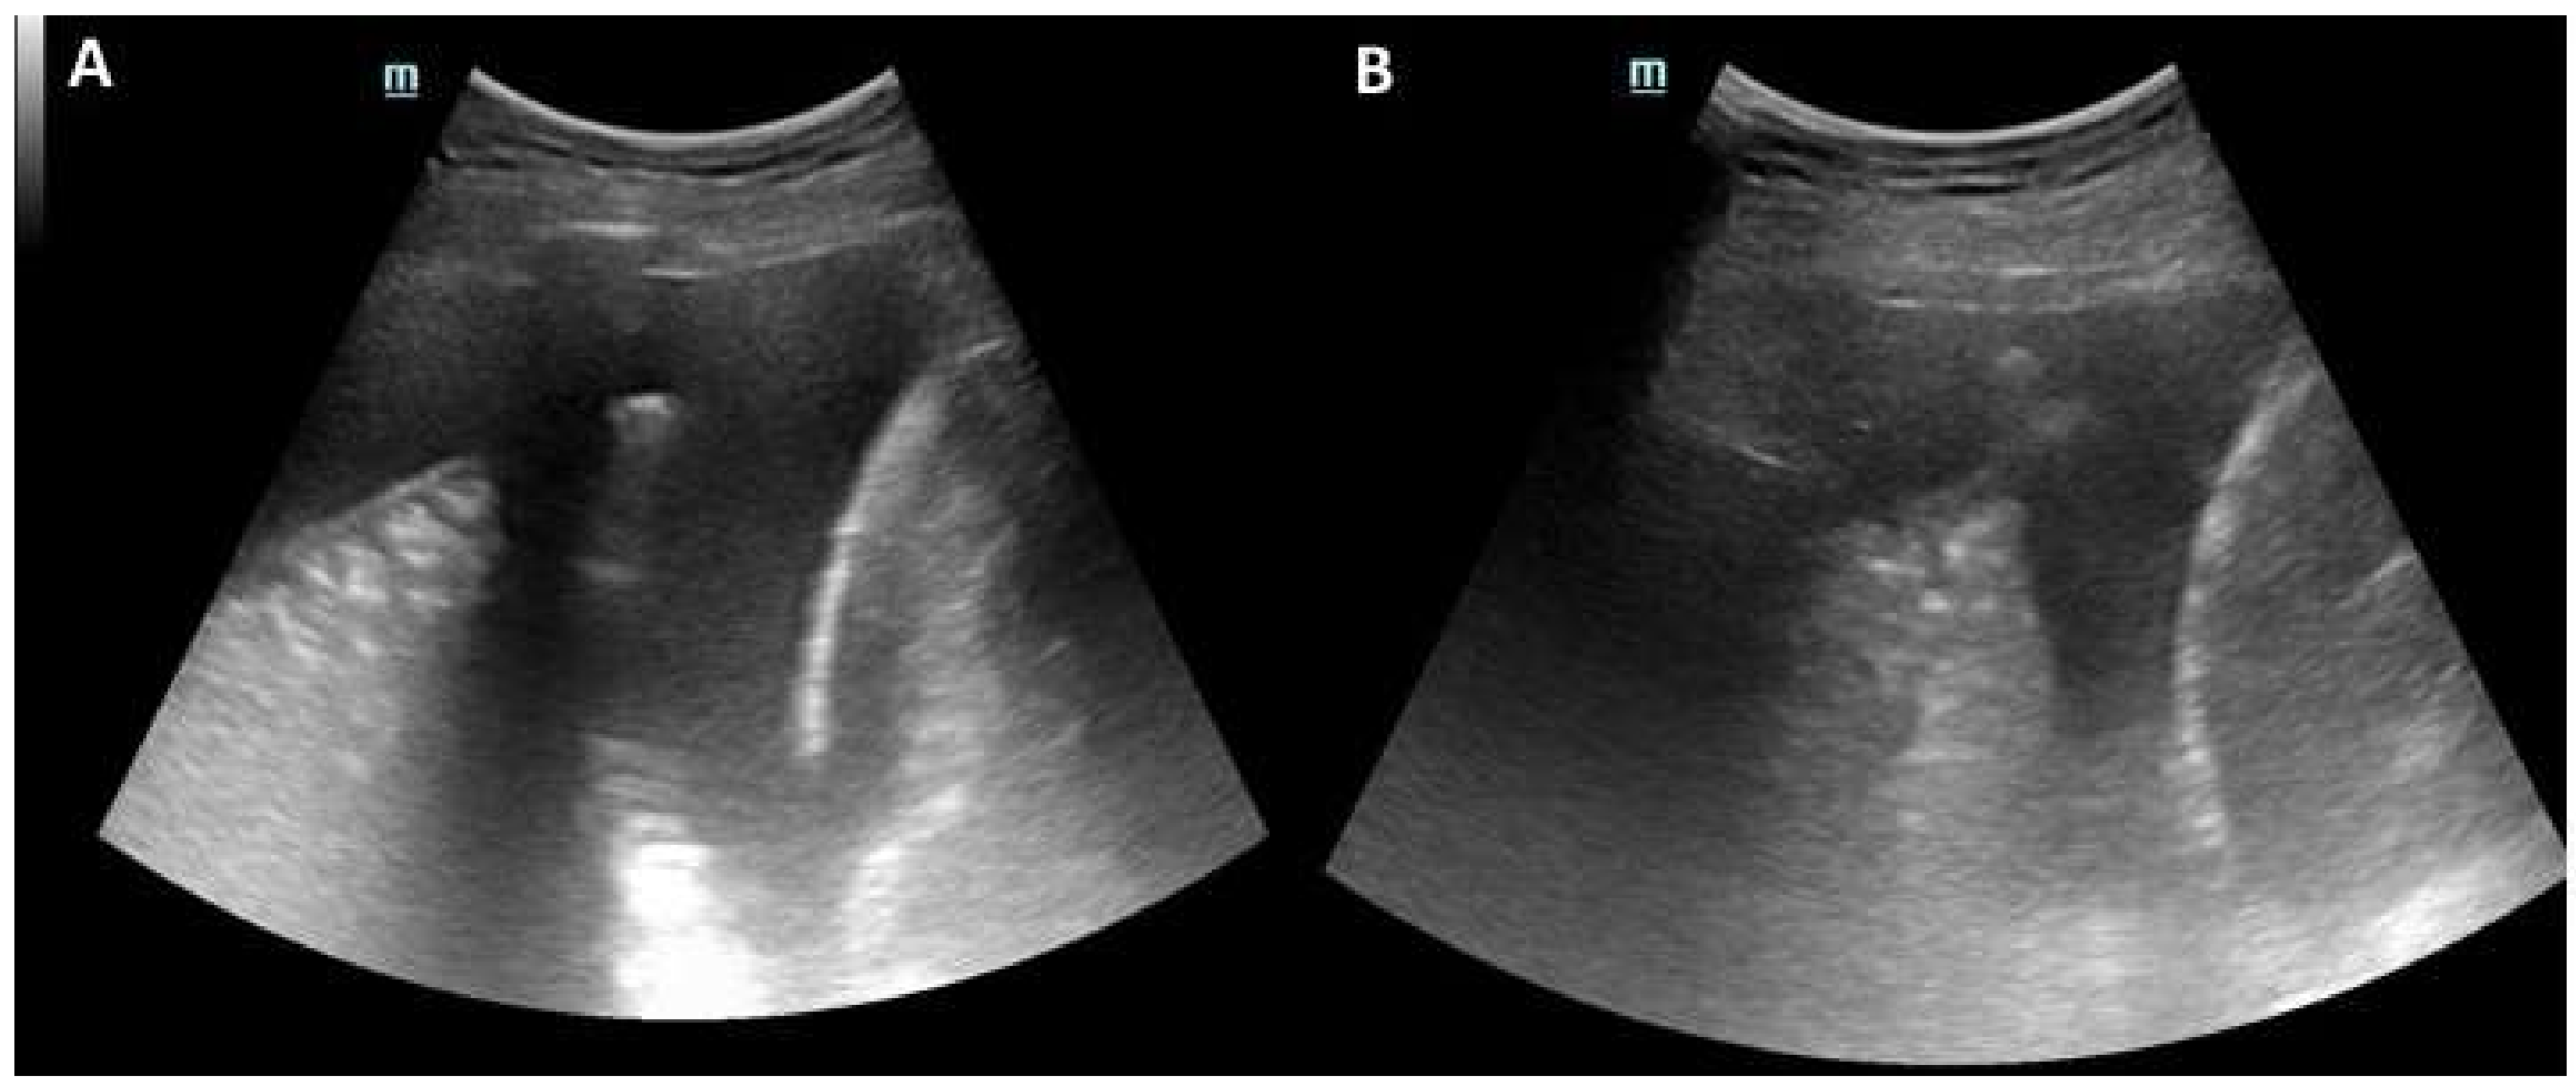

2. Case Presentation